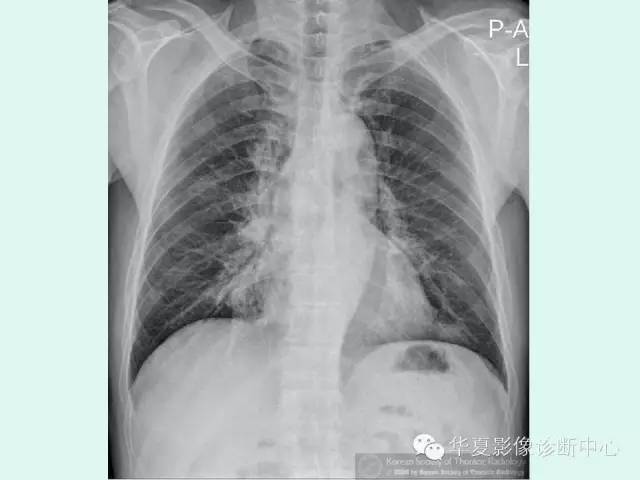

【病例】肺泡蛋白沉积症1例CT影像表现